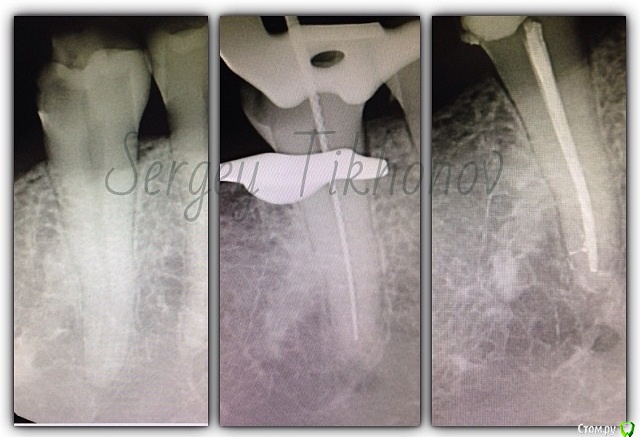

SSTi Опубликовано 15 января, 2015 Автор Поделиться Опубликовано 15 января, 2015 Немножко эндо 24. Резорцин старый. 35.04-45.02. 14-15. Ситуация плохая. 16 тоже под вопросом. Пока попробуем так. Подвижности нет. 14 пульпит ( сначала обработал его ( 35.04. ). 15 асимптоматич. Апикальный периодонтит( его следом обработал 35.04. Кто-то очень умный на половину небного канала засунул цемент). Запаковались. 13- эндометазоновый рай) перелечка метазона. Перед протезированием. На очереди 15. Снимок до на пленке. 3 Ссылка на комментарий